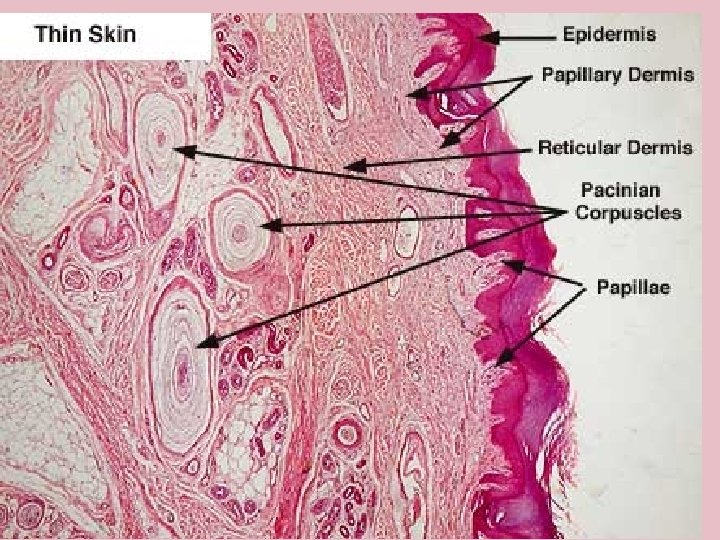

TYPES OF SKIN • Thin skin – covers all parts of the body except for the palms and palmar surfaces of the digits and toes. – lacks epidermal ridges – has a sparser distribution of sensory receptors than thick skin. • Thick skin (0. 6 to 4. 5 mm) – covers the palms, palmar surfaces of the digits, and soles – features a stratum lucidum and thick epidermal ridges – lacks hair follicles, arrector pili muscles, and sebaceous glands, and has more sweat glands than thin skin.

Specific Layer of the Skin Epidermis: • Composed of keratinized stratified squamous epithelium Dermis: • Papillary region composed of areolar tissue • Reticular region composed of dense irregular connective tissue Hypodermis: • Composed of areolar tissue with abundant adipocytes

Layers of the Dermis • Reticular region: consists of dense irregular CT Contain most of the accessory Structures 3. Papillary Region: Consist of areolar Tissue 4. Dermal Papilla: Fingerlike projections that greatly increase surface area 4 3 1 2

Special Sensory apparatus of the dermis Meissner’s Corpuscles: • Present in dermal papilla • Specialized sensory neuron nerve endings • Respond to touch • Most numerous in thick or non-hairy skin of the palmar and plantar surfaces

Special Sensory Apparatus of the Dermis Pacinian Corpuscle: • Encapsulated sensory nerve ending • Located at the hypodermis/dermis junction • Respond to pressure